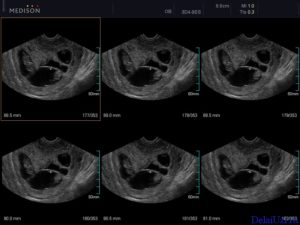

Двойню на УЗИ можно увидеть и определить уже на 4-5 неделе беременности. Как правило, однояйцевые близнецы определяются позже, чем разнояйцевые (не раньше 12 недели).

Самый ранний срок, когда можно выявить, произошло ли зачатие, — 5 недель. В это время врач уже способен разглядеть эмбрионы в матке и определить их количество. На этом сроке начинает формироваться детское сердце, и уже с 8-й недели прослушивается ритм двух или более сердечек. Это также сигнализирует о многоплодной беременности.

Считается, что точно увидеть несколько эмбрионов, можно только при помощи УЗИ. На каком сроке определяют многоплодную беременность? Специалист может увидеть данный факт в 5-6 недель. Но, как правило, ее диагностируют во время первого скрининга в 12 недель.

Самый ранний срок, когда по УЗИ различим плодный мешочек – это 4 недели и 3 дня при условии, что менструальный цикл женщины 28 – 30 дней. Но двойню пока никакой аппарат не определит. Это возможно лишь на 8 акушерской неделе.

Увидеть развитие многоплодной беременности можно на пятой акушерской неделе. При этом разнояйцевые близнецы специалистом определяются раньше, чем однояйцевые.